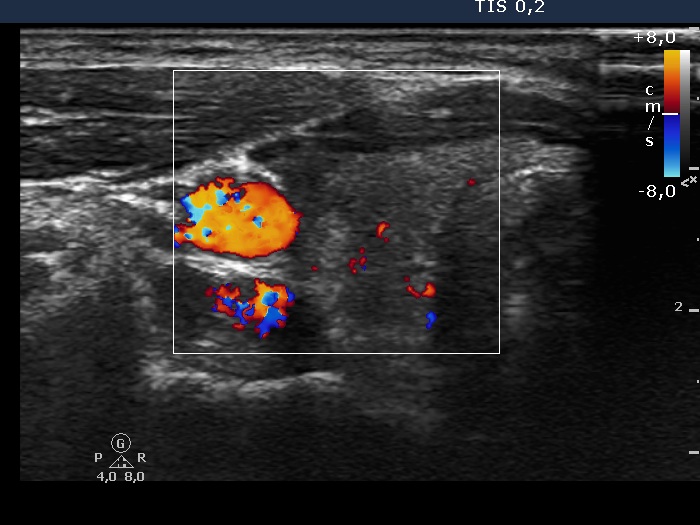

Extrathyroidal spread - case conp 030 (ultrasonographic picture 4)

Right lobe, transverse view, color Doppler mode. There is no vascularization in the nodule in the ventro-lateral part of the lobe.